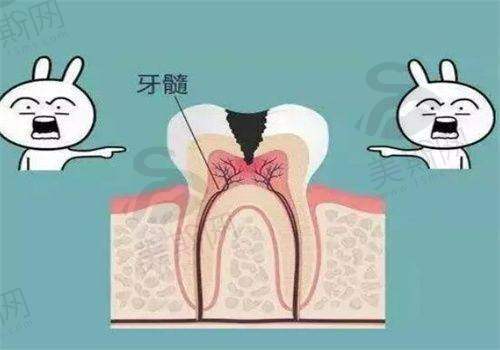

4. 牙周病系统治疗:针对牙龈炎、牙周炎等牙周疾病,采用龈下刮治、根面平整、牙周手术等综合治疗方法,有效控制炎症,保护牙周组织健康。

6. 口腔综合治疗:涵盖补牙、拔牙、根管治疗、智齿拔除等基础诊疗项目,采用微创技术和舒适化治疗方案,减轻患者痛苦。

10. 广东广州柏德口腔(海珠院区)根管治疗:800 - 1500元/颗